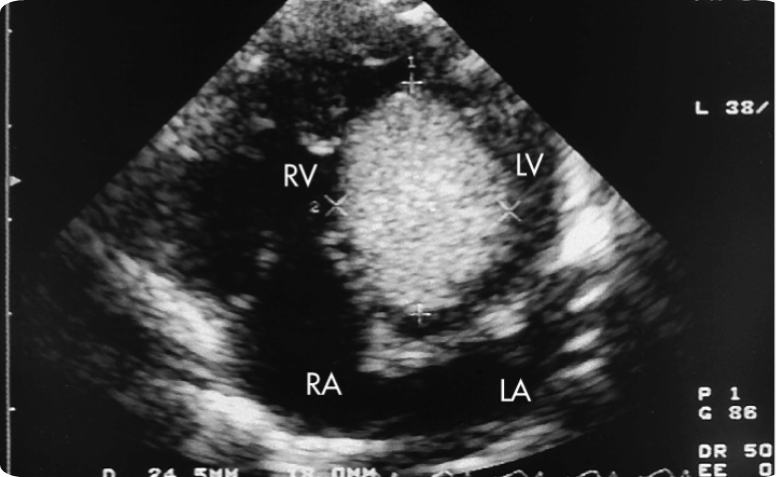

What view is a single ventricle best evaluated in?

4-chamber

What is present and absent in a heart that only has one ventricle?

One ventricle

Two atrium

Mitral and Tricuspid valves